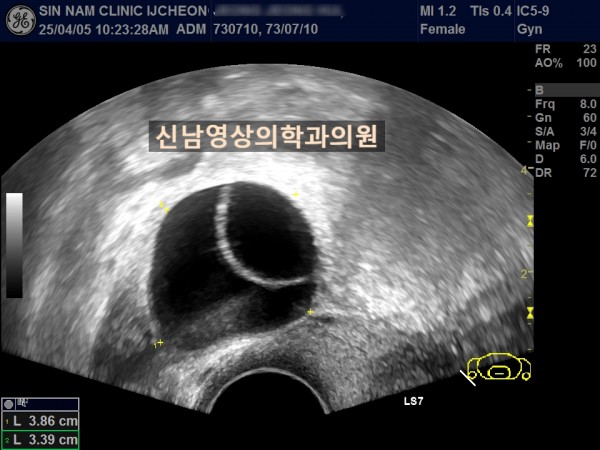

본원에서의 하복부 초음파 시행 사례입니다.

연령 : 52세

하복부 통증으로 내원하셨고, 초음파 검사상 자궁선근종과 난소낭종이 발견되었고, 난소암 혈액검사를 진행했습니다.

난소암 혈액검사 결과는 정상범위로 약간 높은 수치였기에 생리 끝나고, 다시 추적검사를 진행하기로 했지만 복통이 심해져 수술 진행했고, 수술장에서는 암의 가능성이 없는 것으로 전달 받았으나 최종 조직검사상 난소암으로 진단되었습니다.